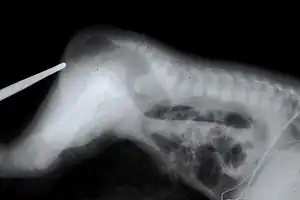

![]() | |

| An example of the defect after which CES is named | |